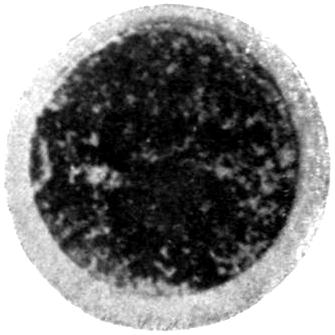

Plate I. 92

Plate II. 93

Plate III. 95